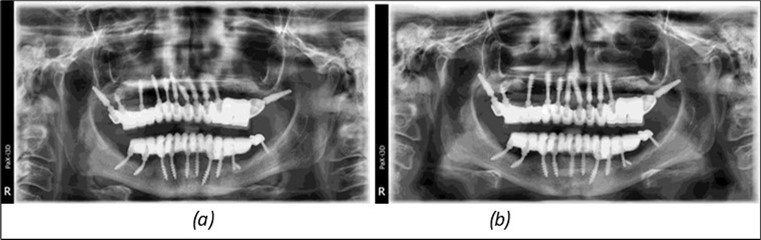

Figure 14.Rx panoramic final situation control: (a) Panoramic X-ray with the addition of a distal BCS implant in quadrant 3 at 11.2022; (b) Control X-ray, 10.2023.

Rx panoramic final situation control: (a) Panoramic X-ray with the addition of a distal BCS implant in quadrant 3 at 11.2022; (b) Control X-ray, 10.2023.

The results of rehabilitation treatment with corticobasal and compressive implants with a polished surface after the failure of two stage implants were highlighted over a period of 3 years and 3 months as being very good (Figure 14, Figure 15), with the patient completing a satisfaction survey in this regard. Certainly, it is necessary to continuemonitoring these results in the long term.